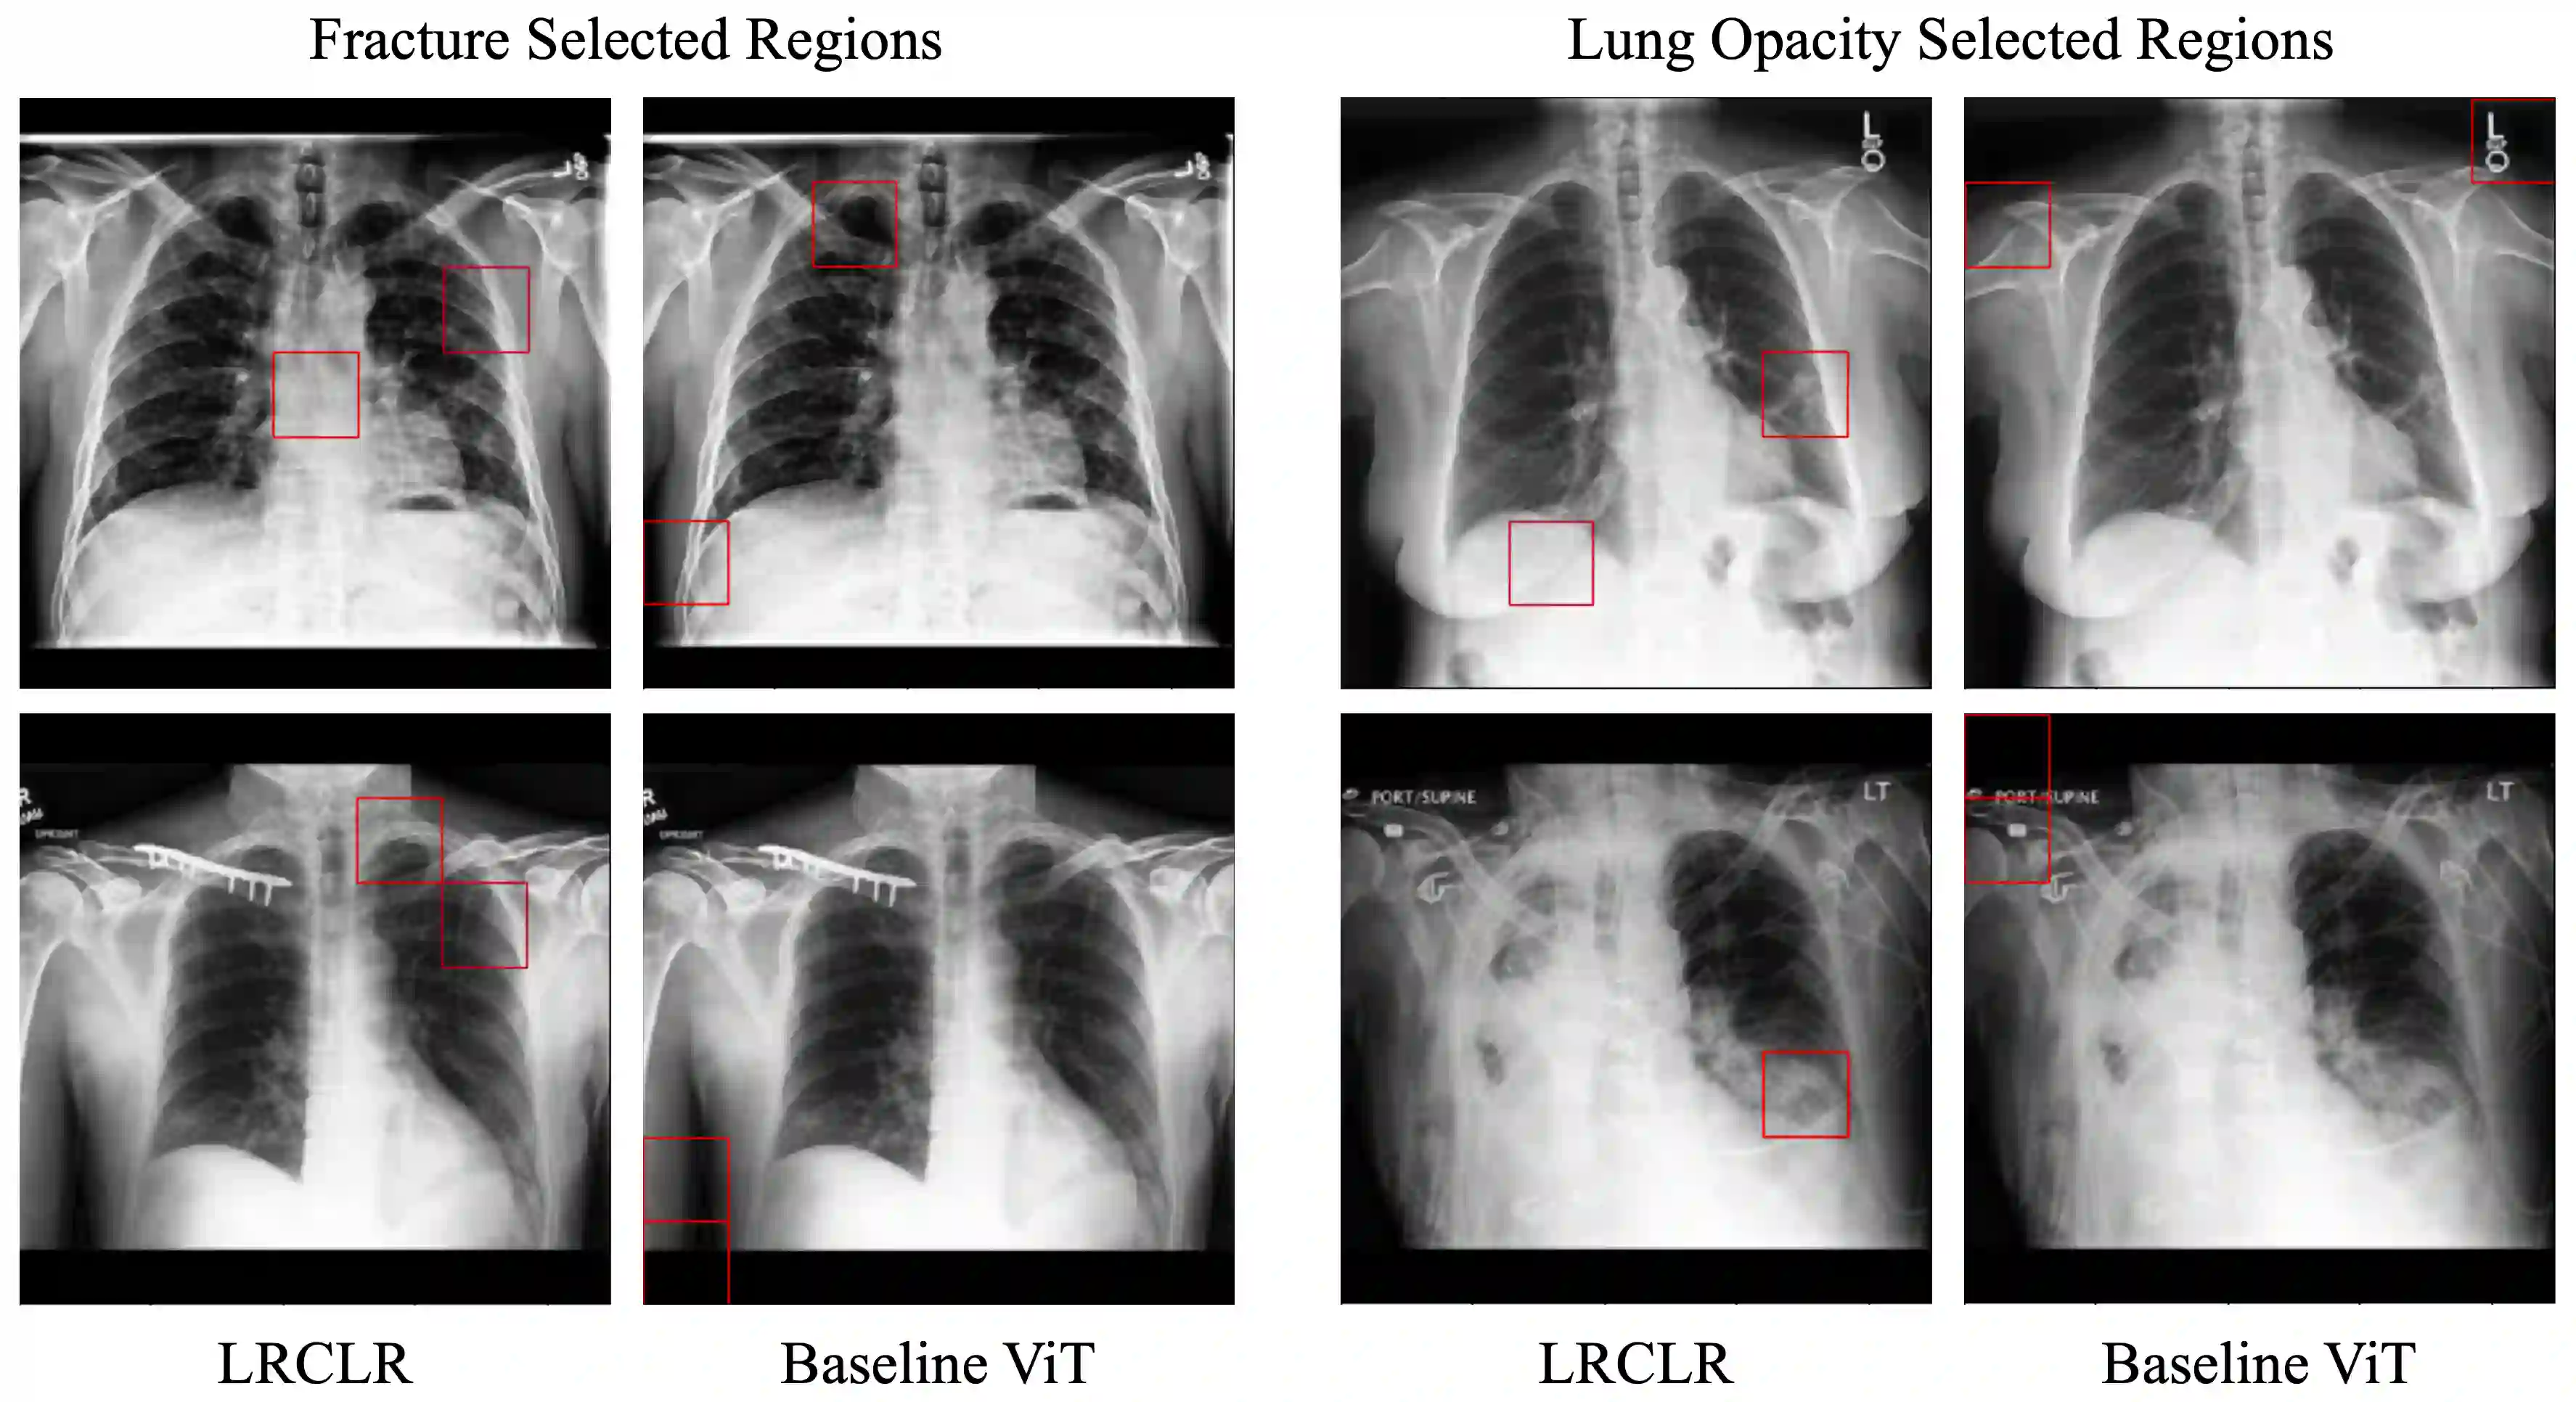

The proliferation of Deep Learning (DL)-based methods for radiographic image analysis has created a great demand for expert-labeled radiology data. Recent self-supervised frameworks have alleviated the need for expert labeling by obtaining supervision from associated radiology reports. These frameworks, however, struggle to distinguish the subtle differences between different pathologies in medical images. Additionally, many of them do not provide interpretation between image regions and text, making it difficult for radiologists to assess model predictions. In this work, we propose Local Region Contrastive Learning (LRCLR), a flexible fine-tuning framework that adds layers for significant image region selection as well as cross-modality interaction. Our results on an external validation set of chest x-rays suggest that LRCLR identifies significant local image regions and provides meaningful interpretation against radiology text while improving zero-shot performance on several chest x-ray medical findings.